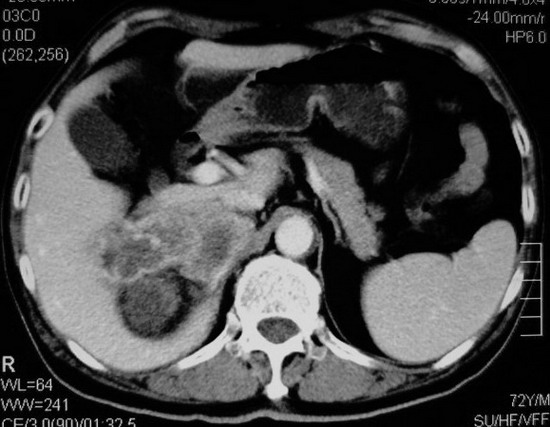

以下是引用杀毒软件在2008-11-17 19:15:00的发言:[br]考虑------右肾癌合并肾静脉---同侧肾上腺受侵可能性大

以下是引用zjzjr在2008-11-17 20:45:00的发言:[br]考虑------右肾癌合并肾静脉---同侧肾上腺受侵可能性大及腹膜后淋巴结转移.